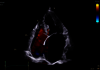

Des images nettes, une clarté instantanée

Découvrez une clarté et une précision d'image extraordinaires

Conçue pour vous emmener plus loin, la nouvelle génération de cSound Pioneer se combine avec notre technologie de sonde avancée pour fournir des détails améliorés, un nouveau standard de flux couleurs et une incroyable imagerie 4D pour une confiance clinique dès le premier scan.